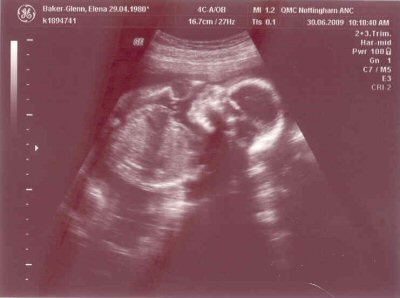

- The scan photos shown below were from the 20 week scan which was done on the 30th June 2009 when the gestational age was 21 + 2 weeks.